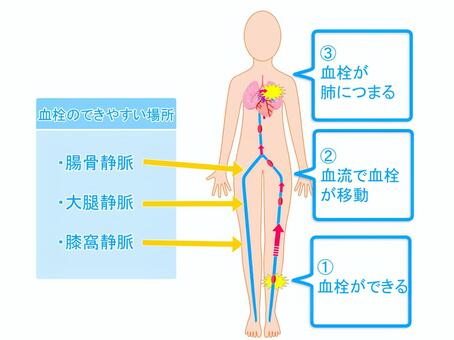

川崎 静脈血栓塞栓症浅田内科・循環器内エコノミークラス症候群。

川崎 静脈血栓塞栓症浅田内科・循環器内エコノミークラス症候群。

エコノミークラス症候群震災時に起こりやすい健康問題と予防法 1看護roo! カンゴルー。

エコノミークラス症候群 深部静脈血栓症 メカニズムのイラスト素材29374549- PIXTA。